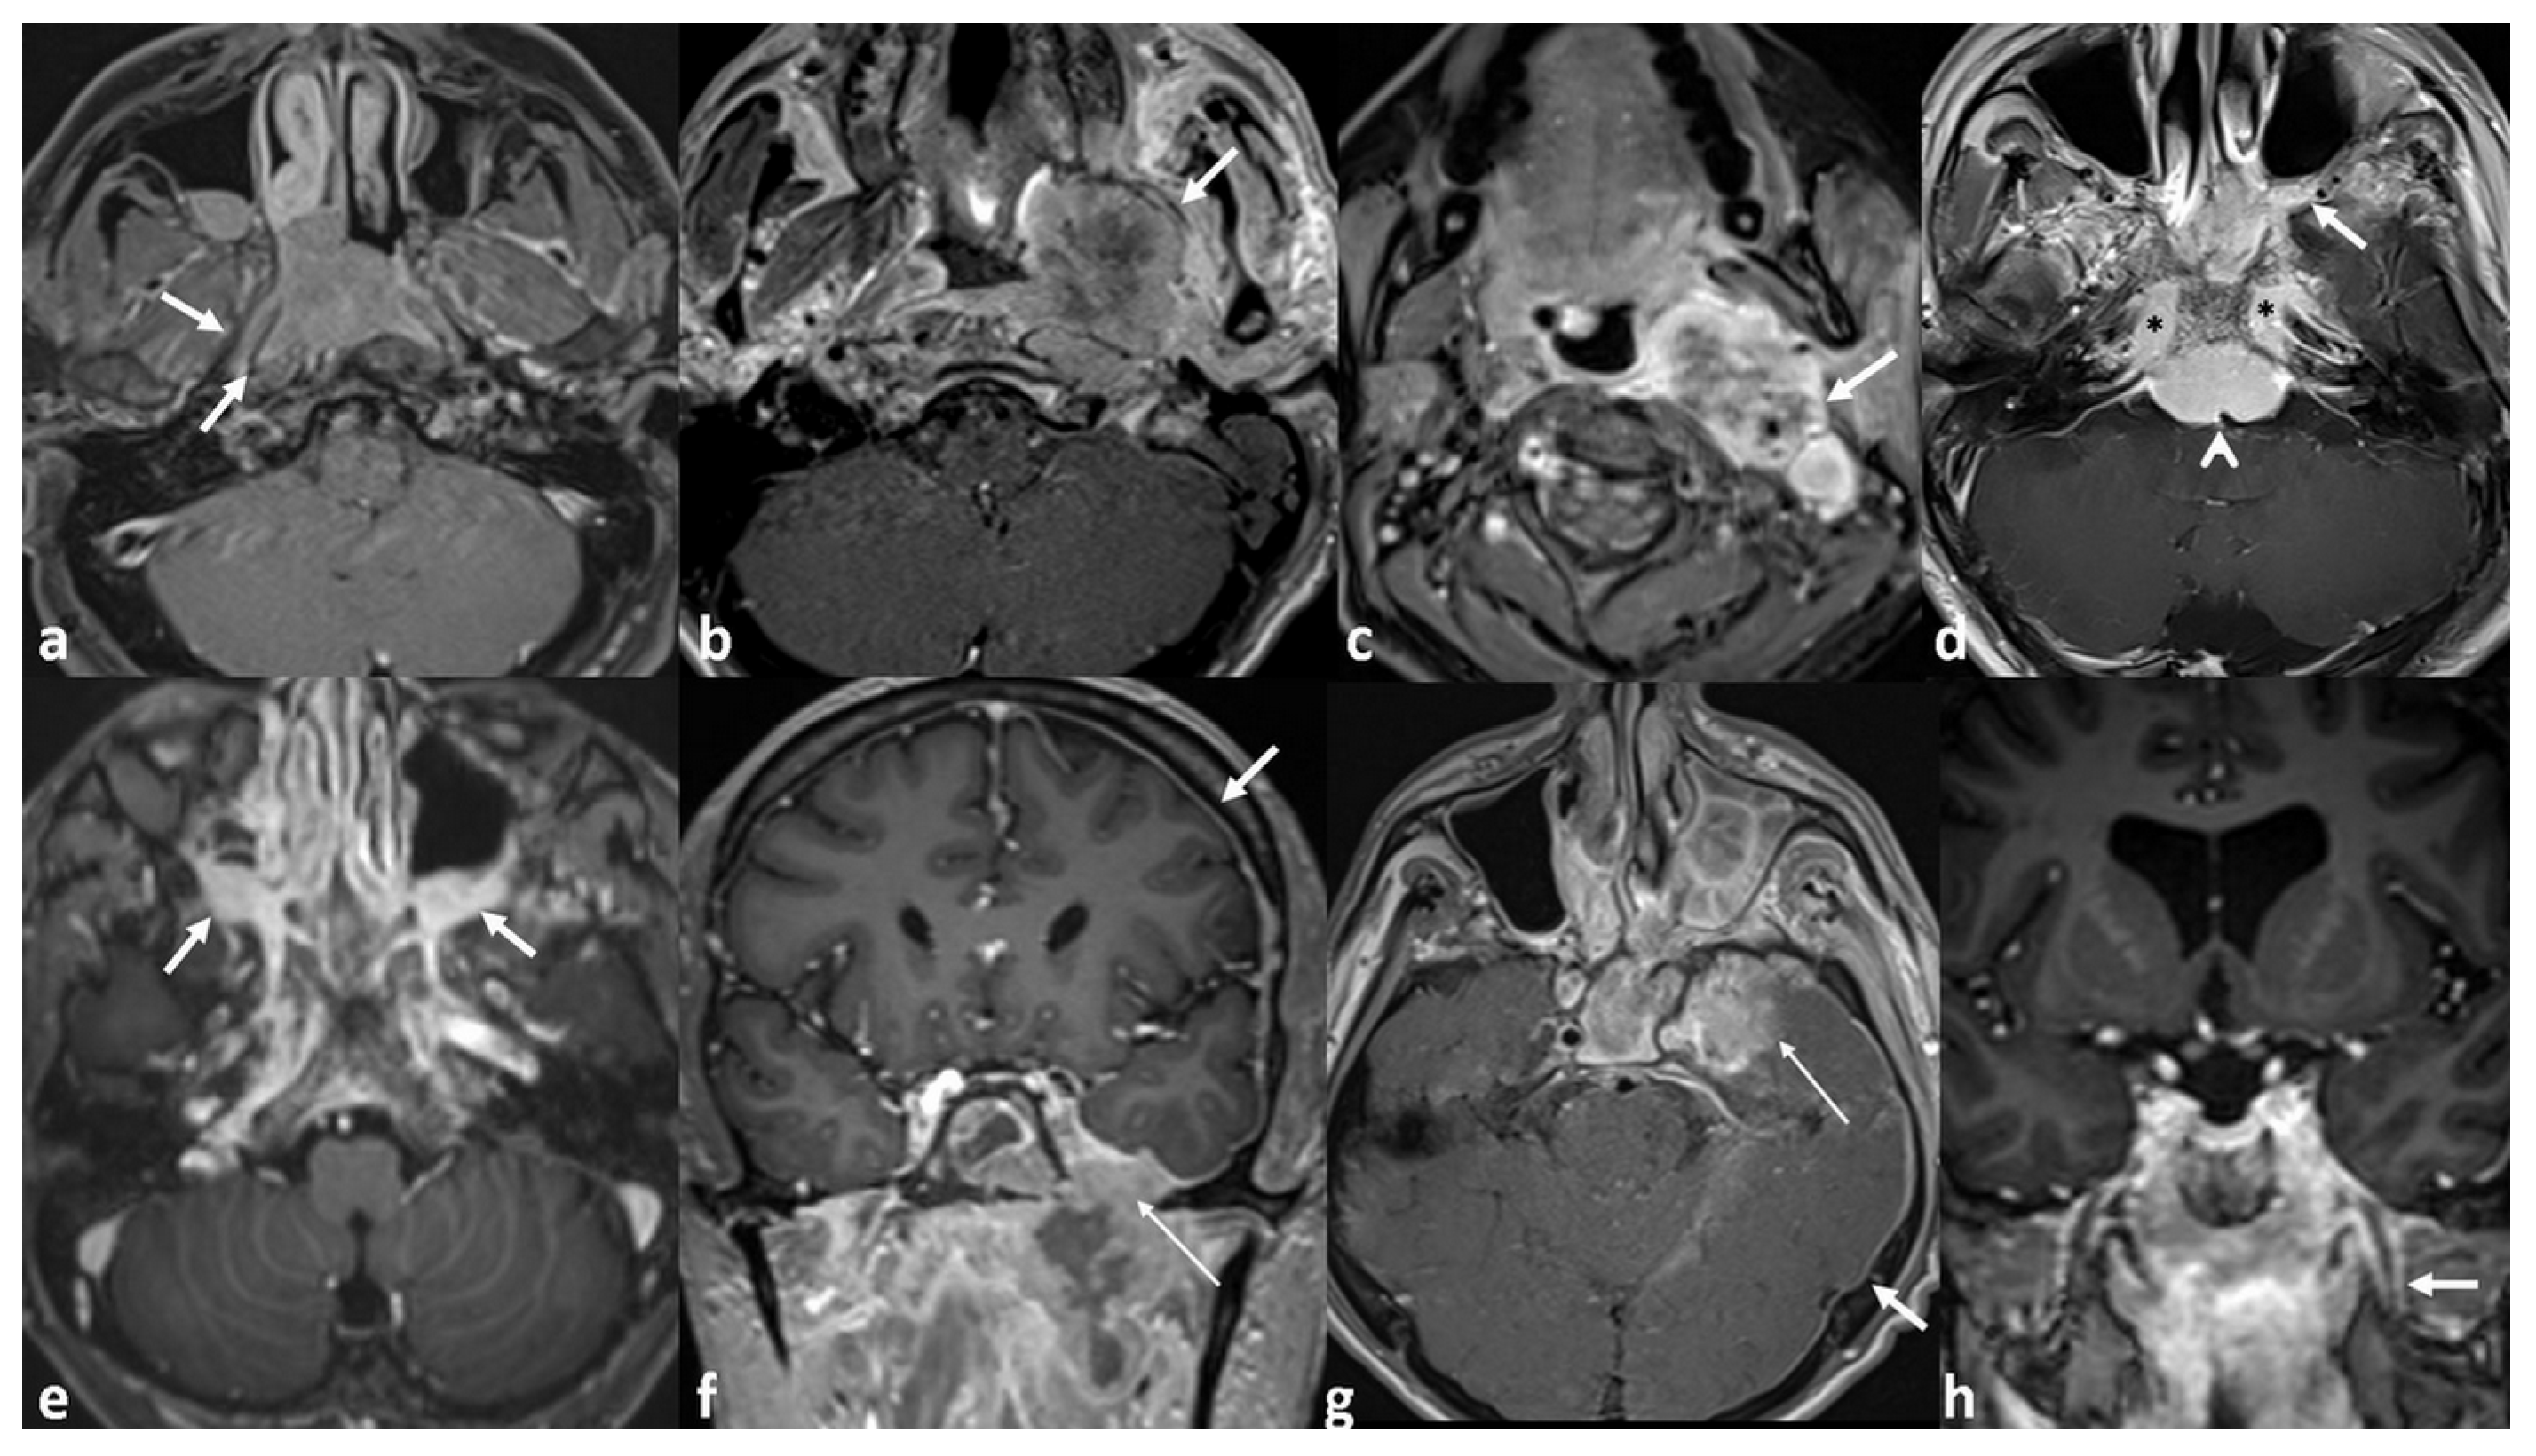

| PPS invasion | 0.001 * | 0.027 * OR: 1.23 95%CI [1.03–1.49] | |

| No | 1/9 (11.1%) | ||

| Local | 3/27 (11.1%) | ||

| Extensive | 10/16 (62.5%) | ||

| ICS invasion | 0.008 * | 0.076 | |

| No | 7/41 (17%) | ||

| Local | 5/8 (62.5%) | ||

| Extensive | 2/3 (66.6%) | ||

| Perineural invasion | <0.001 * | 0.029 * OR: 1.60 95%CI [1.05–2.43] | |

| Positive | 7/43 (16.2%) | ||

| Negative | 7/9 (77.7%) | ||